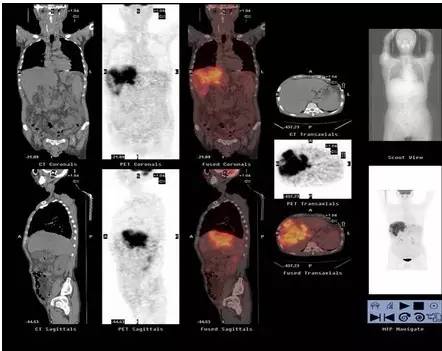

作为核医学的代表,PET/CT是将PET与CT技术融为一体,通过一次显像,可以获得全身各个部位的断层图像,具有特异及定位精确等特点。通过PET/CT,最小可以诊断出3-5毫米大小的肿瘤,可一目了然地了解全身状况,达到早期发现病灶、诊断疾病的目的。

除此之外,对于肿瘤病灶,传统的判断方法是监测肿瘤的大小变化。如果治疗后的病灶比治疗前变小了,这说明治疗有效果;但对于大小没变化的肿瘤则无法判定。而PET/CT,则除了能监测肿瘤的大小变化之外,还可以了解到葡萄糖代谢率的变化,通过对代谢率的判断也可以判定治疗是否有效。可见,与传统诊断方法相比,PET/CT有着更大的优势。